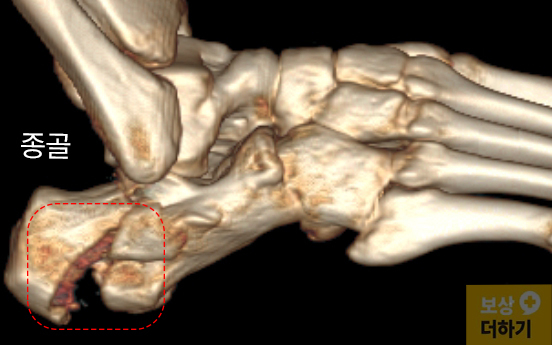

응급실에서 X-ray와 CT 정밀 검사를 진행한 결과, 우측 종골 분쇄골절이 확인되었습니다. 영상 자료(CT, X-ray)를 보시면 종골 부위가 심하게 함몰된 것을 확인할 수 있는데요.